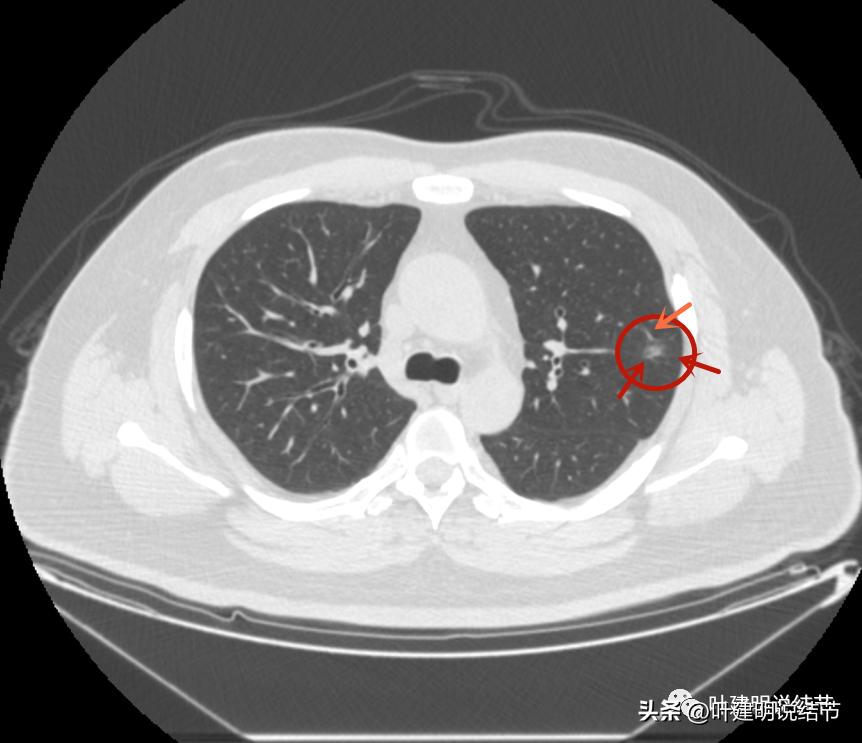

病灶2出现,还只有一点点磨玻璃影,血管走行有点异样

密度略显高,有微血管进入(桔色箭头),边缘略模糊,但轮廓还是较清

中间有实性成分出现(粉色箭头),微血管进入明显(桔色箭头),边上有磨玻璃成分(绿色箭头),整体轮廓清

病灶密度不均

密度不均显杂乱

表面略不平

整体瘤肺边界与轮廓较清

边上另有病灶出现,即左上病灶3(蓝色箭头)